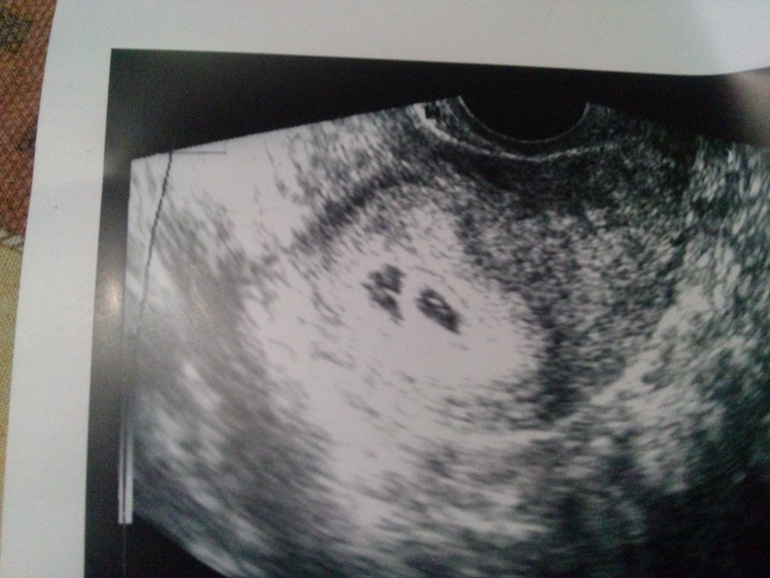

. А контрольная еле её догоняет... Вчера на УЗИ 5 недель +3 дня нашли 2 плодных яйца..

Сказали повтор через 7-10 дней.. Пока перебываю в шоке..

Как же классно,явно оба разовьются ибо в каждом по мешочку есть)поздравляю)